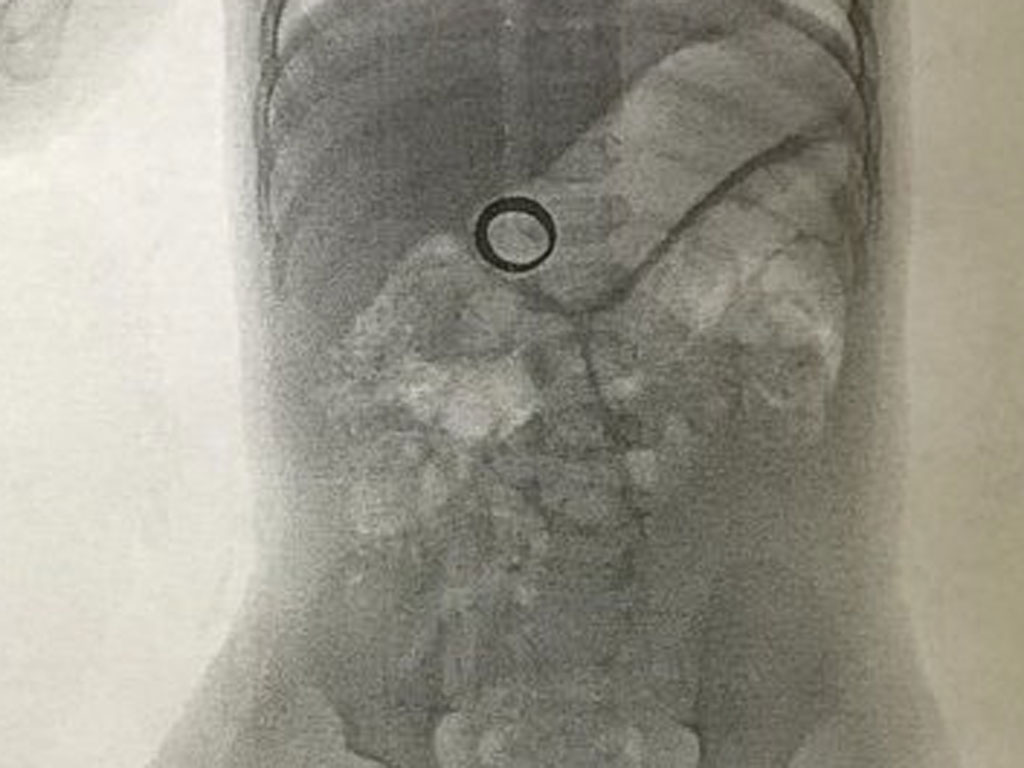

ок проглотил кольцо

Ребенок проглотил кольцо 116 фото